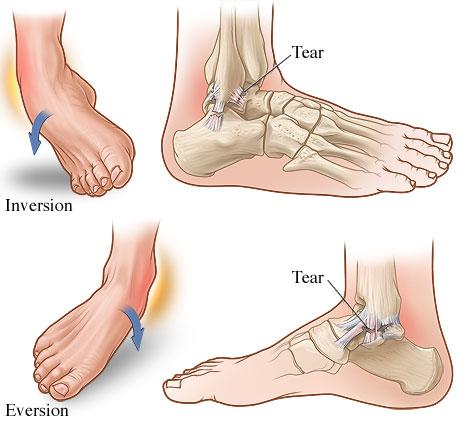

Sprains and strains are arguably the most common injuries caused by participating in sports. A sprain is a stretch or tear of a ligament, which is the connective tissue that joins bones together in your body. A strain is a stretch or tear of a muscle or tendon. Tendons connect your muscles to your bones.